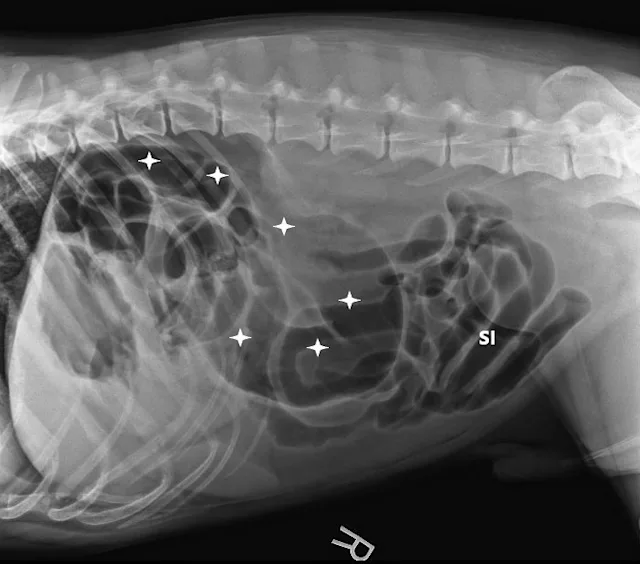

Three-view abdominal radiographs revealed a single bowel loop markedly dilated with gas and amorphous material in the cranial abdomen thought to represent the colon due to its unusual position (ie, could not be tracked from caudal to cranial aspect on lateral radiograph; Figure 1). The small intestines were displaced caudally with no evidence of ileus (ie, gas filled but normal and uniform in diameter), and the descending colon was not fully visualized.

FIGURE 1A

Right lateral (A), left lateral (B), and ventrodorsal (C) abdominal radiographs demonstrating marked dilation of a single bowel loop with gas and amorphous material in the right cranial abdomen, suspected to be the colon (arrows). Caudal displacement of the small intestines (SI) can also be seen. The descending colon (Co) is poorly visualized.